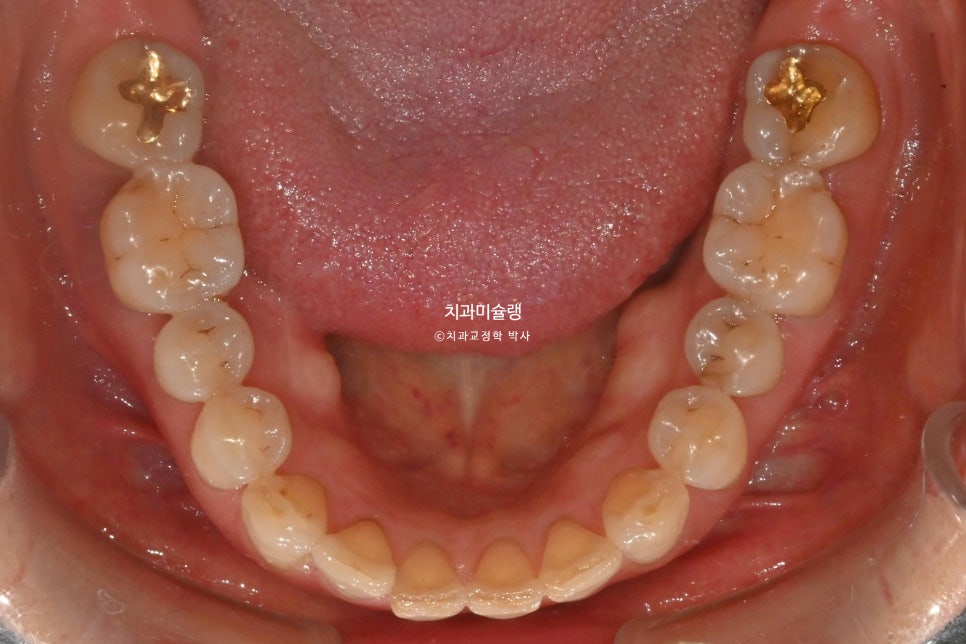

그에비해 아래앞니는 틈도 없고 틀어짐도 경미하죠.

어금니는 배열이나 교합상 문제가 없습니다.

또한 작은어금니부터 큰어금니 까지는 위치를 잠궈놓고 앞니만 움직이는 치료계획을 세우는게 좋습니다. 이렇게 하면 앞니를 제외한 치아들은 교정기간 내내 단 0.1mm의 이동도 없이 교합이 그대로 유지되며, 그만큼 교정치료로 인한 교합 변화로 인한 불편감도 적고 무엇보다 잇몸 부담이 적습니다.